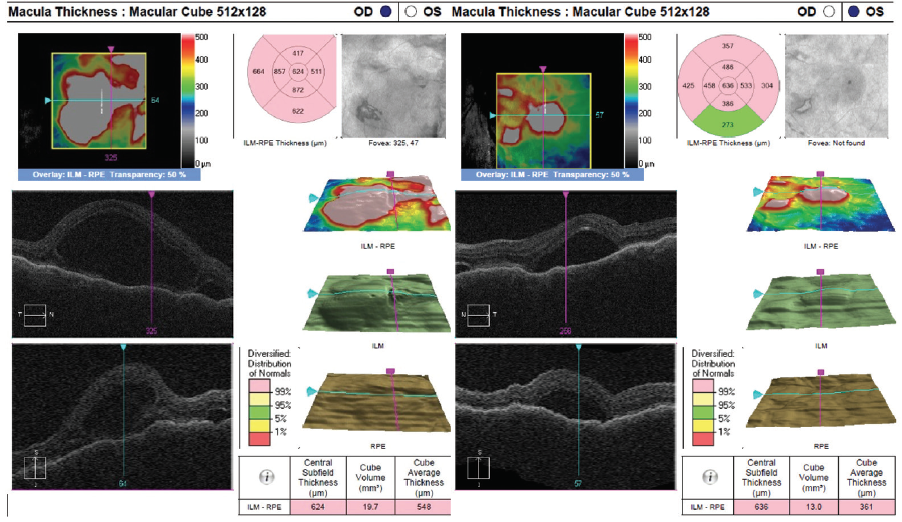

Dilated fundus examination revealed clear media without inflammation OU and numerous deep, discrete, and patchy yellow lesions throughout the posterior pole with irregular borders and multiple areas of distinct retinal elevation OU (Figure 1). The optic nerves were noted to be hyperemic OU without significant elevation, hemorrhage, or obscuration of vessels. Of note, there was no evidence of peripheral pathology or retinal vasculitis. OCT imaging showed numerous areas of intraretinal and subretinal fluid pockets of varying size with notable retinal and choroidal undulation through the macula (Figure 2). Fluorescein angiography showed multiple irregular patchy and pinpoint areas of hyperfluorescent foci throughout the posterior pole with leakage and distinct pockets of pooling in the later frames (Figure 3).

Figure 2. OCT shows multiple pockets of intraretinal and subretinal fluid with undulation of the retina and choroid OU on initial presentation.